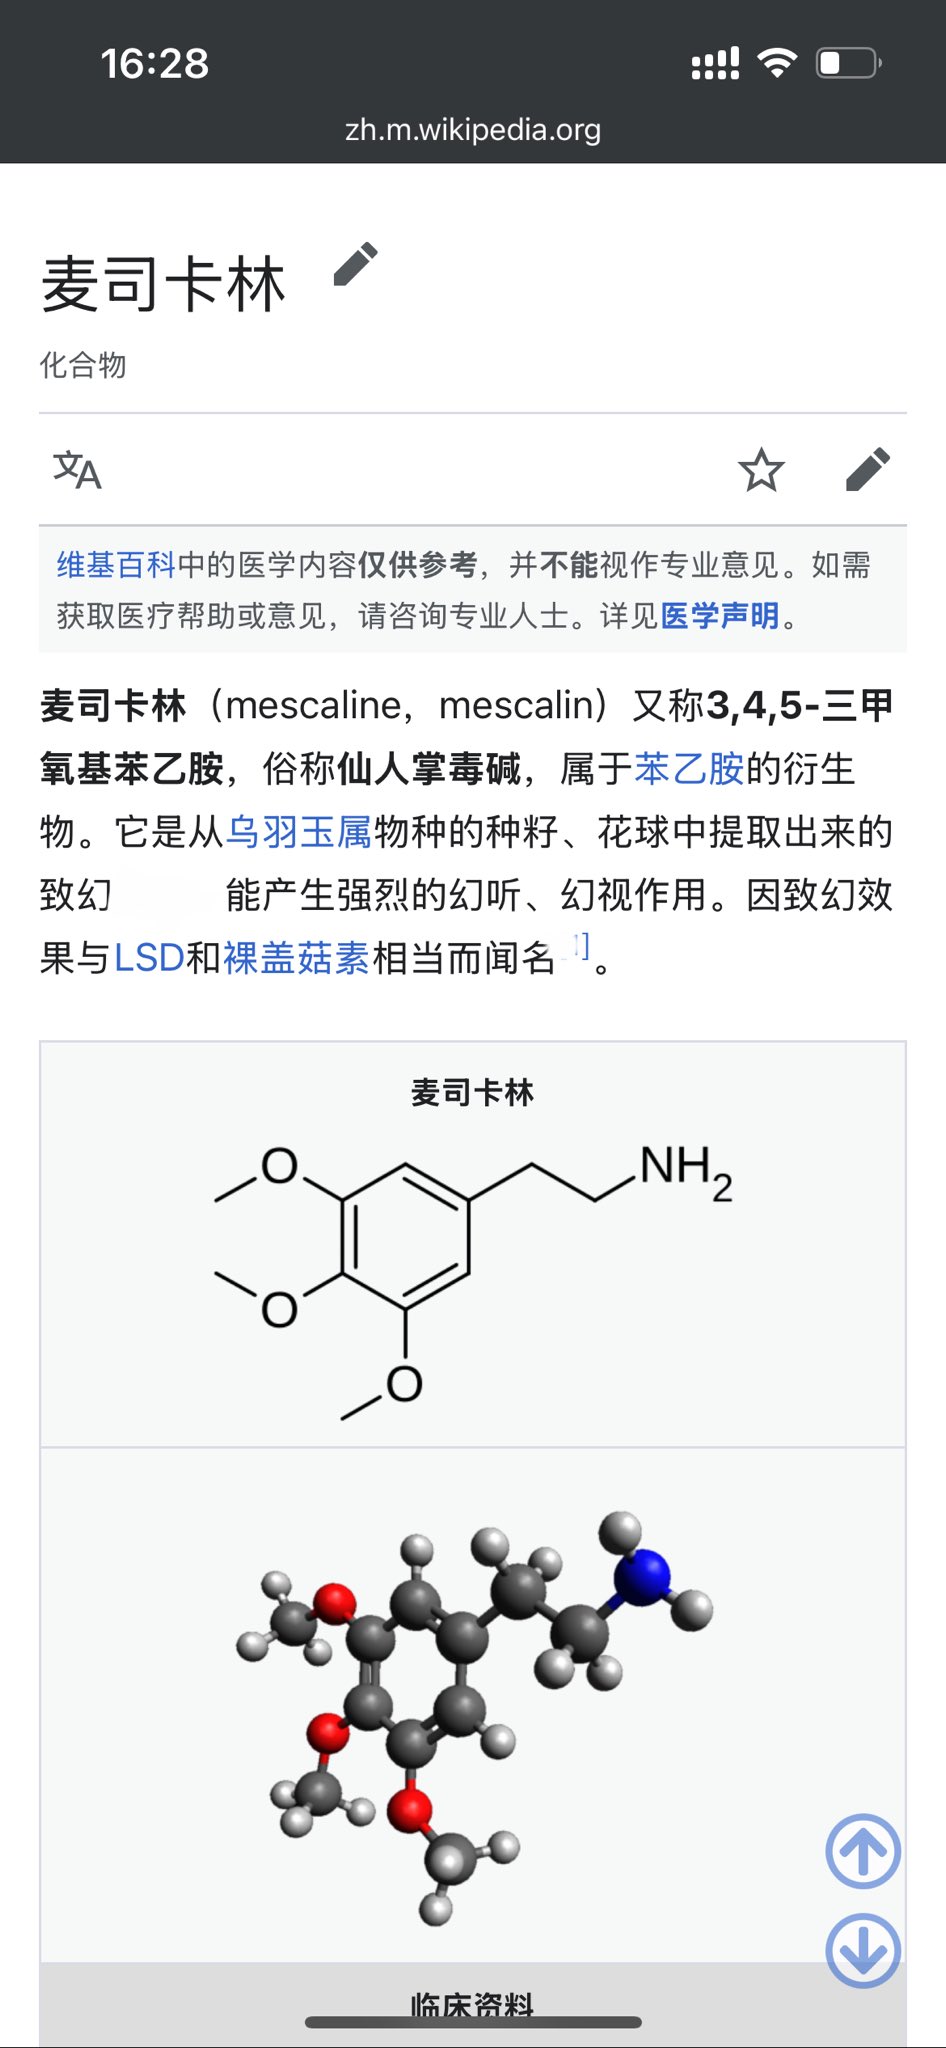

首先,从定义上讲,“反解离(anti-dissociative)”并不是一个标准的医学术语或者广泛认同的药理学分类。在正规资料,比如医学文献、维基百科、精神药理学教科书中,目前并没有“反解离药物”这个正式概念。

看上去像是为了描述某类特定效应而创造的术语(可能是nmda受体活性增强),用来对抗因NMDA受体拮抗剂(比如氯胺酮、DXM、PCP等)引发的解离体验(dissociation)。

那么更常见的是将其归入认知增强剂(cognitive enhancers),特别是改善认知连接性(connectivity)和现实感知(reality testing)的类型。

但其实在药理学上,单纯用“受体激动剂”来逆转“受体拮抗剂”的效应,有时会导致过度激活。

对于NMDA受体而言,过强的NMDA活化本身就与兴奋性毒性(excitotoxicity)和精神病样症状(psychotomimetic effects)有关,比如谷氨酸风暴可以引发严重的焦虑、妄想、乃至癫痫。

也就是说,简单地“激动-解除拮抗”在中枢神经系统是很危险的做法,尤其是对于易感个体(如有精神分裂素质的人)。

科学的处理方式一般是通过更细致的调节,比如微调NMDA/AMPA平衡、调节其他辅助途径(如GABA、5-HT、mGluR受体),而不是简单粗暴地用“NMDA增强剂”去顶回去。